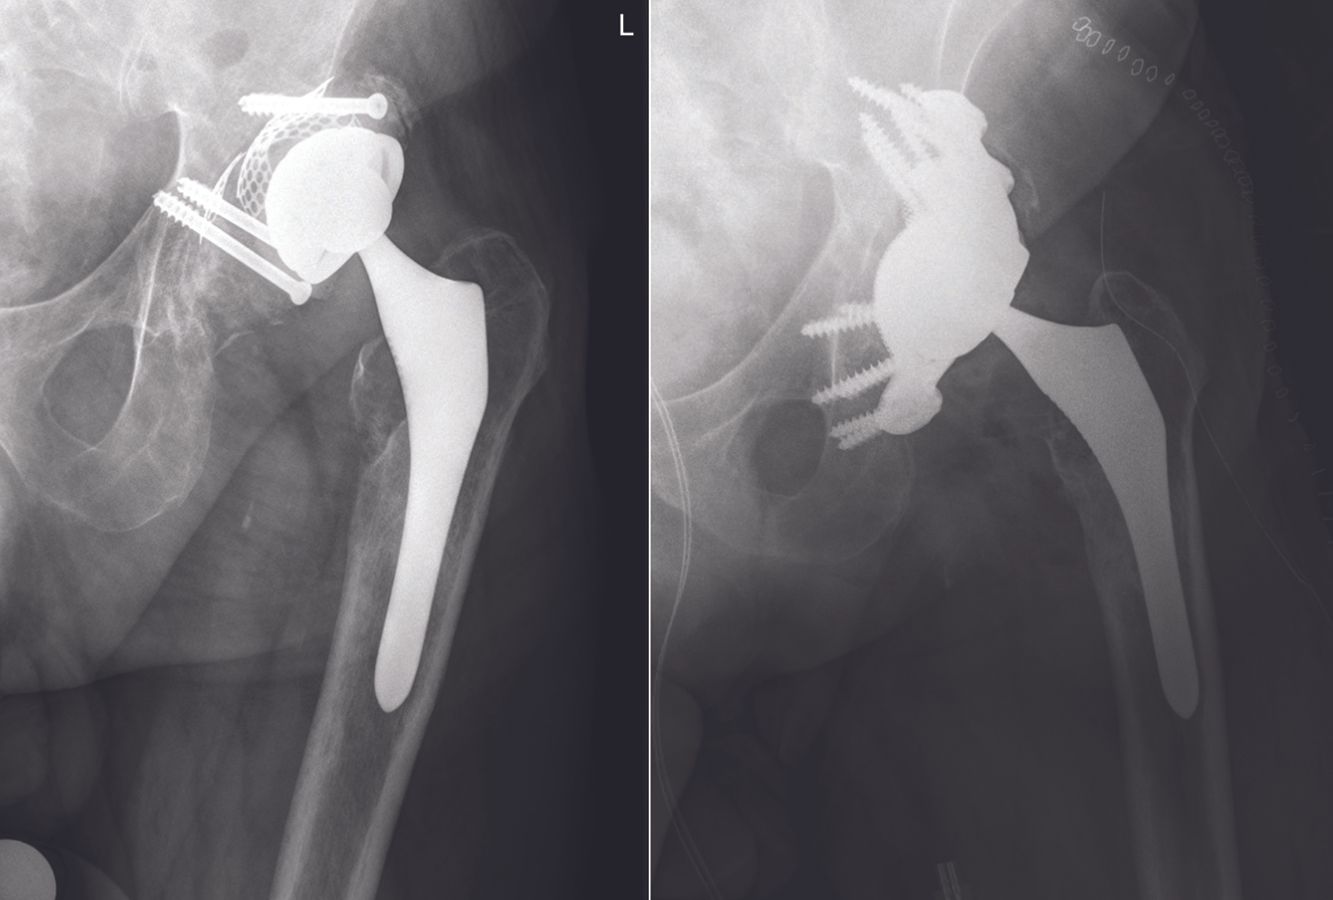

Radiologic follow up showed no signs of migration of the implant or breakage of the screws. Screw loosening occurred in 3 patients without signs of implant loosening or tilting. No revisions of the implants were necessary but 3 re-operations for debridement of delayed wound healing had to be performed (9%). One of these cases had a culture proven deep infection which was treated with additional antibiotics successfully. One patient had a hip dislocation and closed reduction was performed, one patient had a cerebral vascular incident and one had a stress fracture of the ramus inferior (table 2). Existing literature of other patient matched acetabular systems reported re-operation rates up to 35% and revision of the implant in 0-11% of the cases. 5 to 7

Patients will be mobilised with 2 crutches under standard thrombosis prophylaxis for six weeks postoperatively. All patients receive empirical antibiotic therapy until perioperative cultures are negative. If the cultures will be positive the AB therapy is adapted to the pathogen sensitivity and continued for 6 weeks. In order to assess the final position of the implant and screws a CT scan is made postoperatively. A previous study from our group could show good accuracy for positioning of the implant according to the preoperative plan. 4